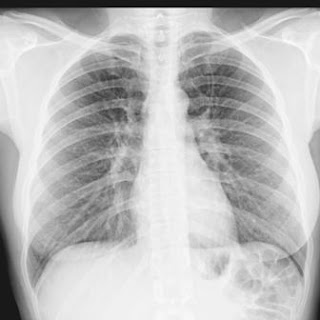

Na medicina os raios X são utilizados nas análises das condições dos órgãos internos, pesquisas de fracturas, tratamento de tumores, câncer (ou cancro), doenças ósseas, etc.

No Brasil, os raios X do pulmão para fins diagnósticos de tuberculose pulmonar são chamados de abreugrafia, que se trata de uma incidência sobre uma pequena área do pulmão.